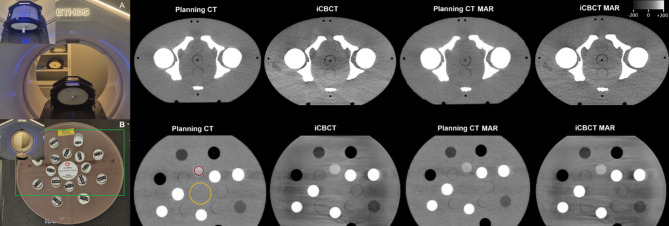

Advanced HyperSight™ imaging for patients with adaptive SBRT of prostate cancer: a longitudinal analysis of tissue demarcation.

Ralf Schmidt, Thanh Nguyen, Alicia S Bicu, Paula Cvachovec, Victor Siefert, Miriam Eckl, Marvin Willam, Matthias F Froelich, Stefan O Schoenberg, Michael Ehmann, Daniel Buergy, Sven Clausen, Jens Fleckenstein, Frank A Giordano, Judit Boda-Heggemann, Constantin Dreher